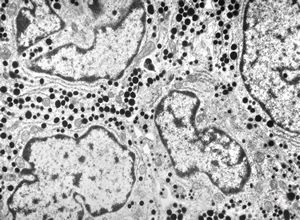

M, 63y. | suprarenal neuroblastoma

M, 3y. | suprarenal neuroblastoma